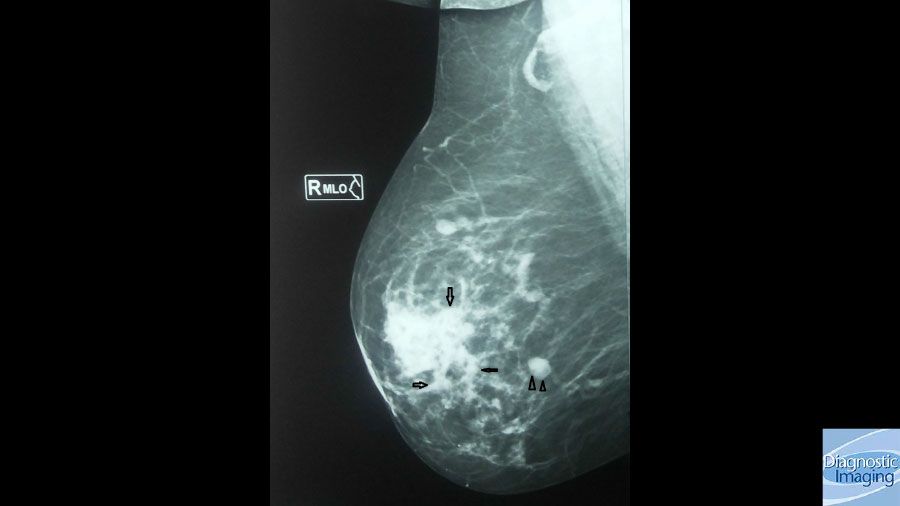

Case History: 49-year-old female presented with palpable right breast retroareolar mass.